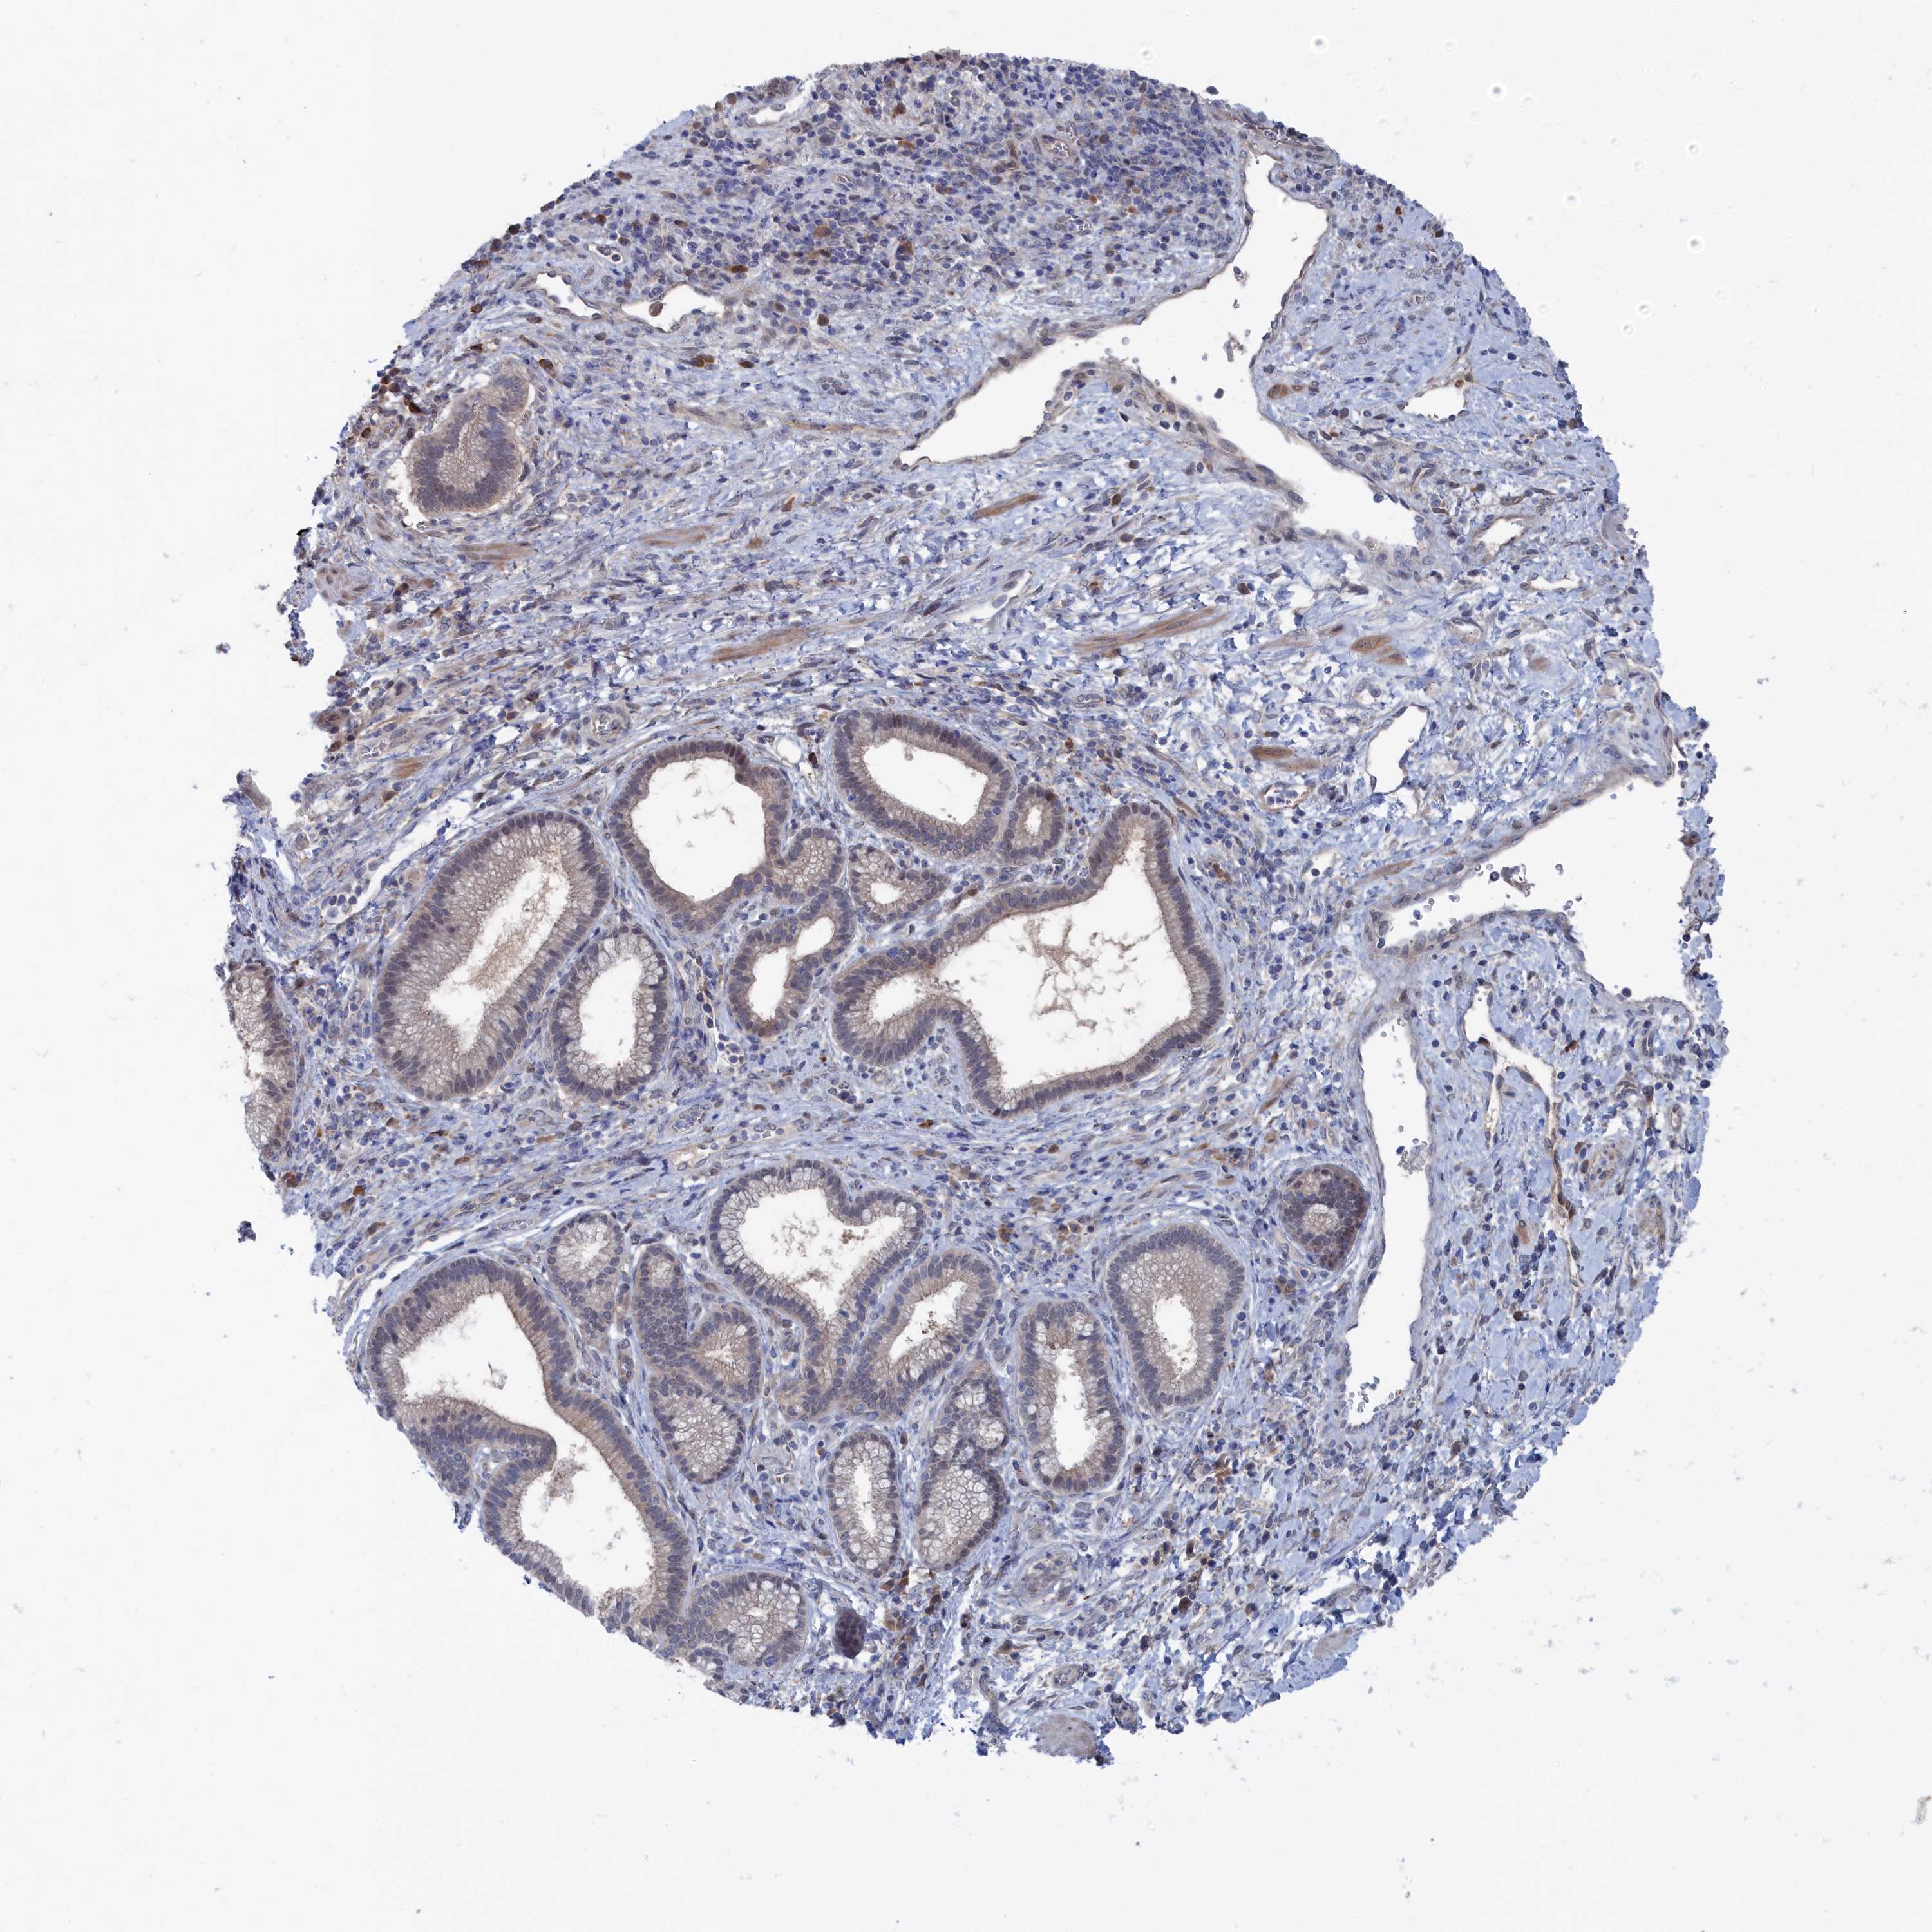

PANCREATIC CANCER - Protein expressioni

A mouse-over function shows sample information and annotation data. Click on an image to view it in a full screen mode. Samples can be filtered based on level of antibody staining by selecting one or several of the following categories: high, medium, low and not detected. The assay and annotation is described here.

Note that samples used for immunohistochemistry by the Human Protein Atlas do not correspond to samples in the TCGA dataset.

Antibody stainingi

Antibody staining in the annotated cell types in the current human tissue is reported as not detected, low, medium, or high, based on conventional immunohistochemistry profiling in selected tissues. This score is based on the combination of the staining intensity and fraction of stained cells.

Each image is clickable and will lead to virtual microscopy that enables deeper exploration of all samples and also displays staining intensity scores, fraction scores and subcellular localization as well as patient and tissue information for each sample.

Antibody HPA043254

Staining

High

Medium

Low

Not detected

Intensity

Strong

Moderate

Weak

Negative

Quantity

>75%

75%-25%

<25%

None

Location

Nuclear

Cytoplasmic/membranous

Cytoplasmic/membranous,nuclear

Adenocarcinoma, NOS